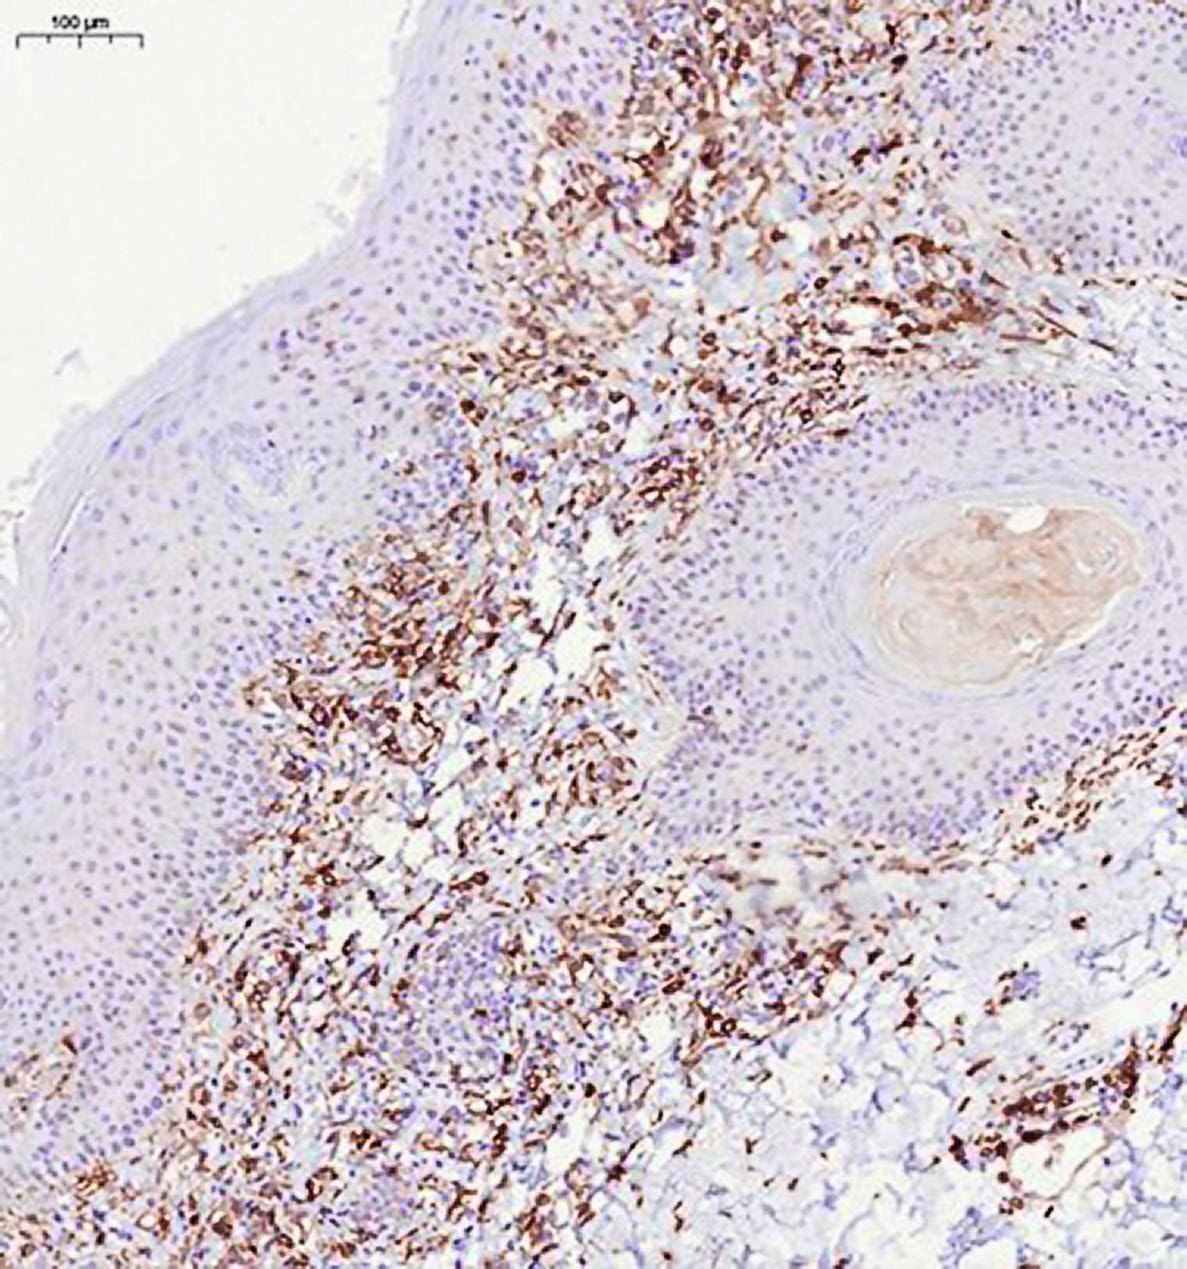

При иммуногистохимическом исследовании антиген пролиферативной активности Ki-67 экспрессирован в ядрах примерно 30% клеток воспалительного инфильтрата, в эпидермисе экспрессия Ki-67 не ограничена клетками базального слоя, а видна в более высоких слоях (рис. 5). Лимфоидные клетки инфильтрата экспрессируют CD3, CD5, соотношения CD4 и CD8 позитивных клеток соответствуют примерно 1:1 (рис. 6, 7). Единичные клетки экспрессируют CD20 (рис. 8). Заключение: клиническая картина заболевания, обнаруженные морфологические изменения в коже и результаты иммуногистохимического исследования в наибольшей степени соответствуют атипичной форме красного волосяного лишая Девержи.

Рис. 5. Иммуногистохимическое исследование с антителами к Ki-67, ×100

Рис. 6. Иммуногистохимическое исследование с антителами к клеткам CD4+, ×100

Рис. 7. Иммуногистохимическое исследование с антителами к клеткам CD8+, ×100